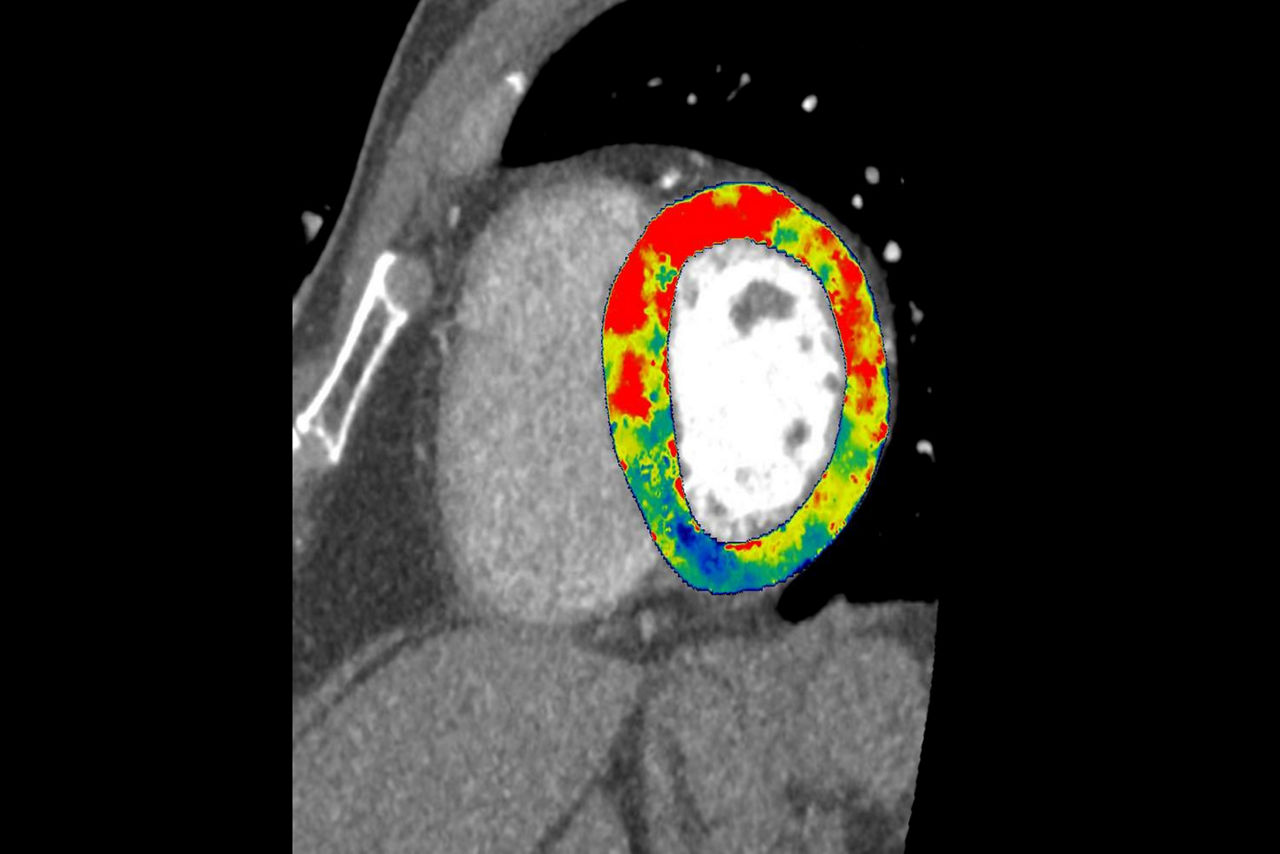

Dynamic CT Myocardial Perfusion Protocol

The dynamic myocardial perfusion protocol is laid out in a series of three easy to follow steps. Start by selecting the series that has been generated from the non-rigid registration protocol and then follow the guided workflow:

• Cardiac Reformat– images are automatically orientated into short and long axis views

• Segmentation–define the valve plane and the apex of the heart. The software will then calculate the endocardial and epicardial borders and provide a 17 segmented map of the myocardium along with a graphed view for each segment.

• Functional Maps – the third and final step produces the quantitative data with the color overlay and bullseye maps for blood flow, blood volume, mean slope of increase and mean transit time.